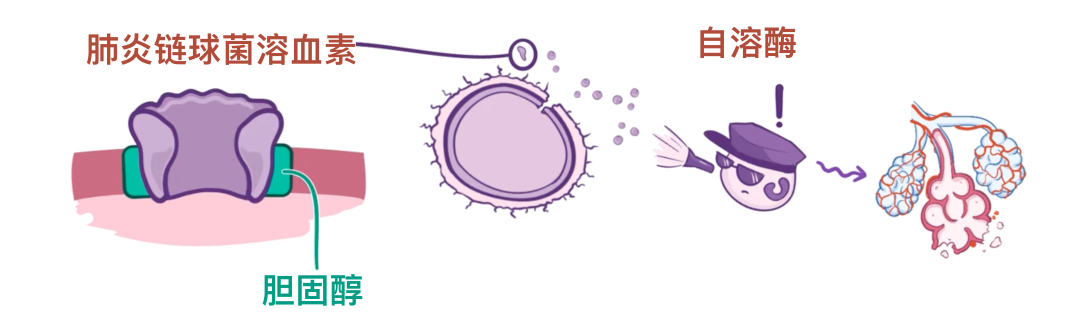

不仅如此,肺炎链球菌还会产生毒素,其中最重要的是 IgA 蛋白酶和肺溶素。

IgA 蛋白酶能破坏 IgA 免疫球蛋白,而 IgA 正常情况下会结合入侵细菌,从而让中性粒细胞摧毁它们。换句话说,就好像电脑病毒先把杀毒软件干掉一样。

接下来是肺溶素,它能够激活宿主的补体系统,而补体是一组参与免疫反应的血浆蛋白。

这一过程会导致局部炎症,结果不仅破坏细菌,同时也损伤宿主的组织,例如肺泡毛细血管和肺细胞。